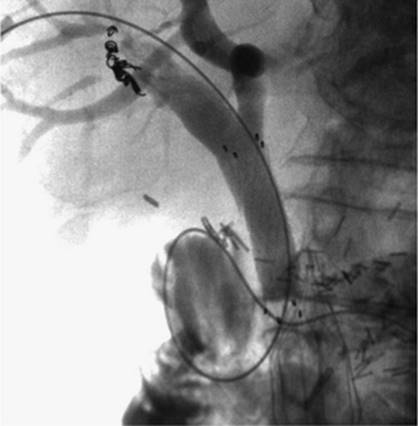

Transjugular intrahepatic portacaval shunting (TIPS) was first conceived of and performed in dogs in 1969 by Josef Rosch et al. (36). The first human case of percutaneous TIPS was reported in 1988 (37). It is an effective nonsurgical and nonendoscopic means to control variceal bleeding by decompressing the portal venous system (38). A CT scan, ultrasound, or MRI is recommended to evaluate for patency of the portal vein as well as exclude hepatic neoplasm and evaluate for other anatomic considerations. The usual laboratory studies to check for hematocrit and coagulopathy should also be performed. IV antibiotics should be administered prior to the procedure. The technique consists of a percutaneous approach, usually ultrasound-guided canalization of the right internal jugular vein. From this approach, access is gained to the hepatic veins and pressure measurements are made from the portal vein using a wedged technique to the right atrium. A hepatic venogram is performed, followed by angiogram of the portal vein, using carbon dioxide and either a wedged technique or puncture of the hepatic parenchyma through the jugular access. Passage of a long curved needle is then performed from a satisfactory location in the hepatic vein, usually the right hepatic vein, into the identified location in the intrahepatic portion of the portal vein or its branches. Direct pressure measurements are made using the transjugular pathway (Fig. 35.20). If acceptable, balloon angioplasty of the intrahepatic tract between the hepatic vein and the portal vein is then performed. A stent, usually covered, is deployed from the portal vein to the hepatic vein through the tract to keep it patent and prevent hepatic recoil and restenosis (Fig. 35.21). Repeat pressure measurements are performed to confirm satisfactory pressures have been reached. Any additional adjustments that need to be made to the stent can be performed at this time, as well as embolization of varices if indicated.

000450

Figure 35.20. Patient with cirrhosis undergoing a transjugular intrahepatic, portacaval shunting (TIPS) procedure. Catheter (white arrow) is positioned from a hepatic venous approach, through the hepatic parenchyma into the portal vein (black arrow). (Image courtesy of Harry K. Meisenbach, MD.)

000280

Figure 35.21. Post–transjugular intrahepatic, portacaval shunting (TIPS) angiogram shows a patent TIPS shunt with a covered stent (black arrow). (Image courtesy of Harry K. Meisenbach, MD.)